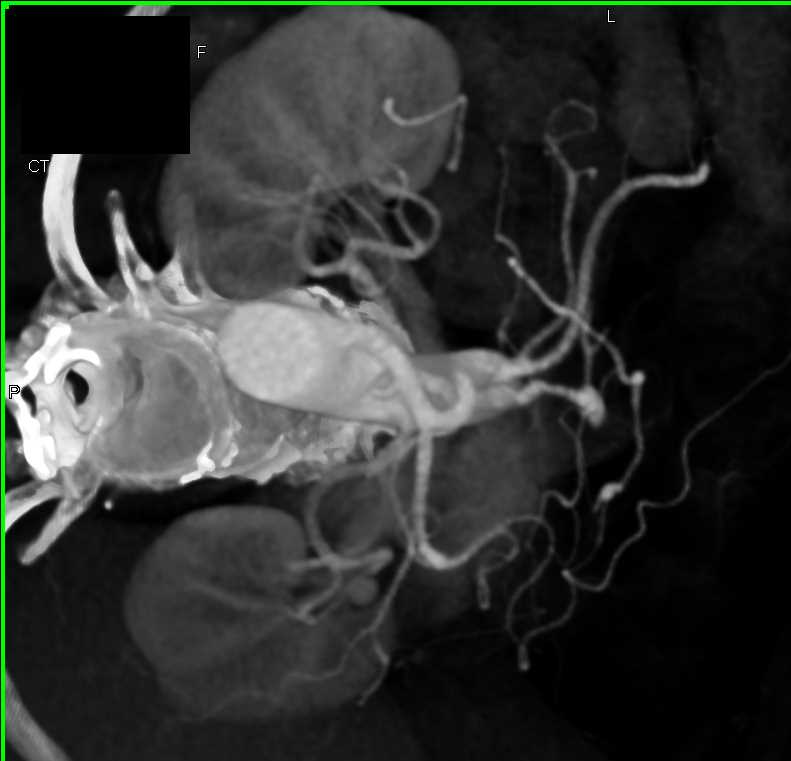

Neuroendocrine Tumor Body of Pancreas